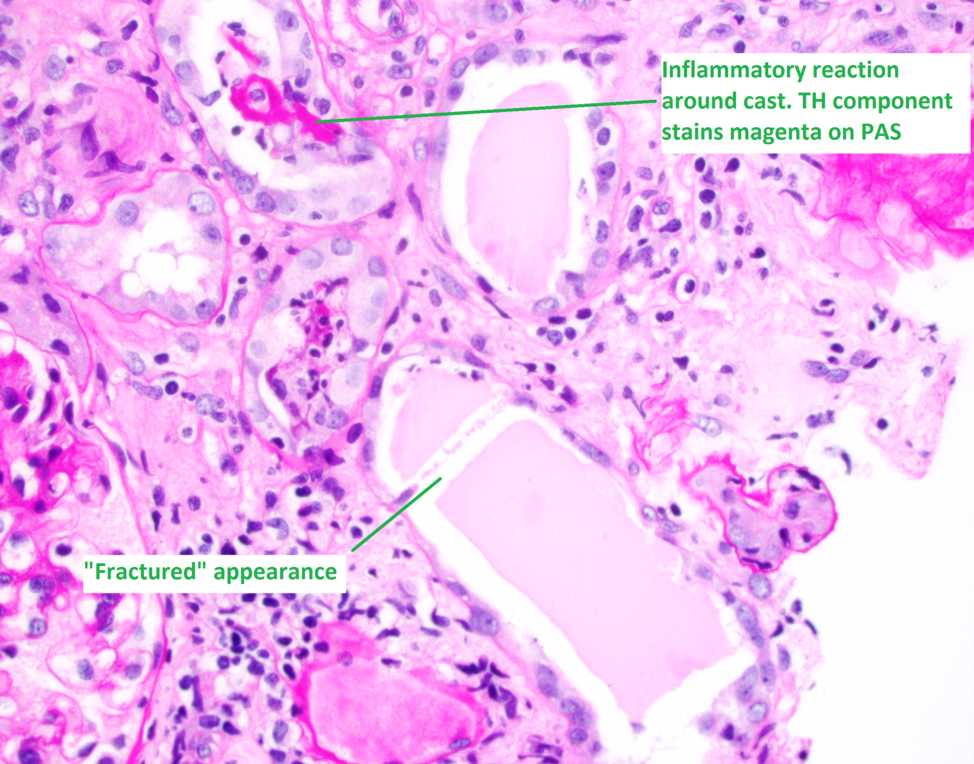

1. Light chain casts have an eosinophilic appearance on H&E stain, with a pale/light pink appearance on PAS. In contrast to this TH protein casts and hyaline casts are positive on PAS, staining a bright magenta color.

2. LC casts usually have a “fractured” appearance on light microscopy. This is a histotechnology sectioning artifact that occurs due to the hard/rigid nature of the casts, which is not seen in TH or hyaline casts which are softer.

3. LC casts elicit an inflammatory response in the adjacent interstitium. The casts themselves are often surrounded by intraluminal macrophages and sometimes multinucleated giant cells.